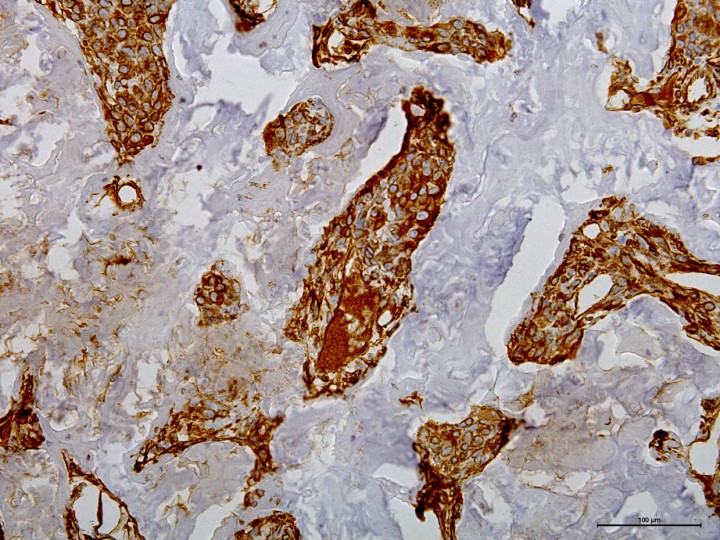

En la disección del globo ocular, las estructuras intraoculares se hallaban ocupadas por tejido calcificado no diferenciable (Fig. 6). El examen histopatológico evidenció la existencia de una proliferación neoplásica mesenquimatosa, moderadamente celular que crecía de forma infiltrativa y ocupando el vítreo, las cámaras anterior y posterior, y reemplazaba la coroides, atravesando la esclera y alcanzando la conjuntiva en la zona del limbo (Fig. 7). Las células neoplásicas crecían en trabéculas y, multifocalmente, de forma más sólida en paquetes densos sobre el estroma fibrovascular, produciendo abundante matriz osteoide que se mineralizaba de forma difusa, con osificación de las mismas, y con lagunas y osteocitos evidentes. La morfología de estas células era poligonal y fusiforme (10-15 μm) con bordes pobremente definidos. El citoplasma era de tamaño variable, eosinófilo homogéneo y con restos de matriz osteoide en algunas de las células. El núcleo era central, de gran tamaño y redondeado con cromatina finamente granular y un nucleolo eosinófilo evidente. El grado de anisocitosis y anisocariosis era moderado y el índice mitótico elevado (2-8 mitosis/40x), siendo algunas de las mitosis aberrantes (Figs. 8 y 9). Algunas células eran bi y trinucleadas. Se observaron extensas áreas de necrosis de las células neoplásicas. Se realizó tinción de inmunoperoxidasa para vimentina con resultado positivo (Fig. 10). La histopatología concluyó un diagnóstico de osteosarcoma ocular y signos de queratitis ulcerativa difusa subaguda grave.

<div class=\"Basic-Text-Frame\">

<p>Histopatología. Trabéculas de células neoplásicas que presentan positividad frente al anticuerpo anti-vimentina. IHQ Vimentina (x20).</p>

</div>

Figura 10

Histopatología. Trabéculas de células neoplásicas que presentan positividad frente al anticuerpo anti-vimentina. IHQ Vimentina (x20).